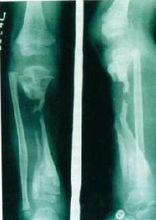

急性化膿性骨髓炎急性化膿性骨髓炎是化膿性骨髓炎的延續,往往全身症狀大多消失,只有在局部引流不暢時,才有全身症狀表現,一般症狀限於局部,往往頑固難治,甚至數年或十數年仍不能

痊癒。對大多數病案,通過妥善的計畫治療,短期內可以治癒。